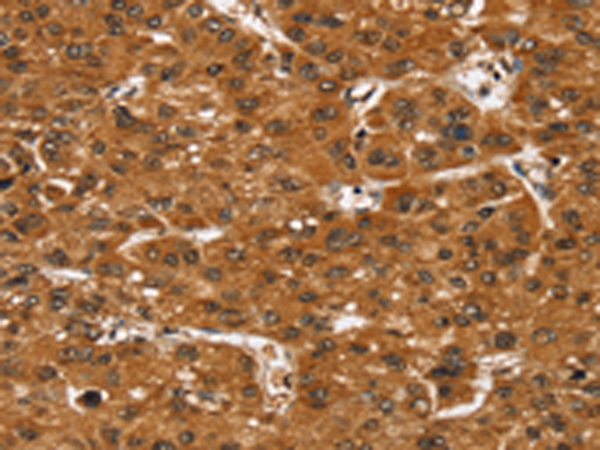

分类: 科研抗体货号: P08760别名: TID1; HCA57; hTID-1应用: IHC反应种属: Human, Mouse